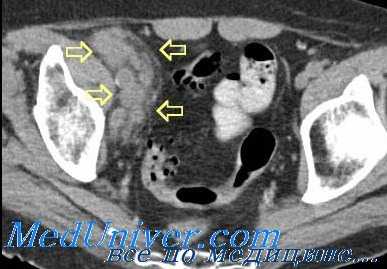

КТ тазовых лимфоузлов при лимфогранулематозе (ЛГМ) - болезни Ходжкина

Поражения лимфатических узлов при лимфогранулематозе (ЛГМ) и неходжкинских лимфомах (НХЛ) различаются. При ЛГМ поражаются преимущественно ретростернальная, перикардиальная, трахеобронхиальная и бронхопульмональная группы; форма поражения — изолированная, пакет, реже инфильтрат. При НХЛ эти группы поражаются менее чем в 15% случаев; форма поражения изолированная, реже в виде пакета и конгломерата.

Предварительная дифференциальная диагностика лимфогранулематоза (ЛГМ) и неходжкиновских лимфом (НХЛ)

| КТ-признаки | Лимфогранулематоз (ЛГМ) (Болезнь Ходжкина) | Неходжкинские лимфомы |

| Возраст | Чаще молодой | Чаще 40-70 лет |

| Стадия | Чаще локализованная | В 85% — генерализованная |

| Частота поражения лимфатических узлов средостения | Более 75% | Менее 25% |

| Частота поражения лимфатических узлов живота: — парааортальные: | Менее 40% | Более 75% |

| — брыжеечные: | Менее 3% | Около 70% |

| Количество групп пораженных лимфатических узлов | 1-2 группы | 3-4 и более |

| Форма поражения лимфатических узлов: — изолированная | Часто, от 6 мм и более | Часто, от 10 мм и более |

| — пакет узлов: | Часто | Часто |

| — конгломерат: | Редко, в средостении | Часто, у 1/3-1/2 |

| — лимфоидный инфильтрат: | Редко | Часто, у 1/3-1/2 |

| Структура лимфатических узлов | Часто однородная | У 1/2 неоднородная с распадом |

| Экстранодальные поражения: — ниже диафрагмы: | Редко | Часто |

| — множественность поражении: | Редко | Часто |